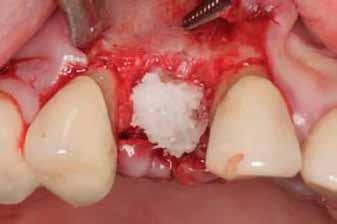

A fogak eltávolítása minimálinvazív módon történt, amelynek során a parodontális rostokat egy periotom segítségével átvágtuk, így lebenyes feltárásra nem volt szükség (3. a–b ábrák) . Az implantátumokat a frissen eltávolított fogak alveolusaiba ültettük be. A foghúzást követően minden alveolust alaposan ellenőriztünk az endodontiai, vagy parodontális eredetű gyulladásos szövetmaradványok eltávolítása érdekében, majd fiziológiás sóoldattal bőségesen átöblítettük. Megfelelő előfúrást követően a kerámiaimplantátumokat 30 fordulat/perc sebességgel és 35 Ncm behajtási nyomatékkal helyeztük be (4. a–b ábrák) . A réseket csontpótlóval töltöttük ki (Maxresorb ® 0,5–1,0 mm szemcseméret, 0,5 cm 3 térfogat, Straumann ®; 6. ábra ).

Tanulmányunk célja összesen négy, rágó területre beültetett kétrészes Zi ceramic implant® kerámiaimplantátum (Neodent) teljesítményének értékelése volt. A legalább tizenkét hónapos utánkövetés alatt egyetlen esetben sem tapasztaltunk technikai vagy biológiai szövődményt, amely bizonyítja az implantátum osszeointegrációjának klinikai és radiológiai sikerét, valamint a lágy- és keményszövetek volumenének stabilitását. Eredményeink összhangban vannak más, azonos implantátumokkal és hasonló utánkövetési periódussal készült tanulmányok tapasztalataival [8, 10]. Korábbi, állatokon végzett vizsgálatok kimutatták, hogy a cirkónium-dioxid implantátumok osszeointegrációja megbízható és biztonságos, még különböző terhelési viszonyok mellett is [11, 12]. Mint azt korábban említettük, jelen tanulmányban mind a négy implantátum sikeresen osszeointegrálódott a vizsgált tizenkét hónap alatt.

Figyelembe véve az itt bemutatott esetek korlátait, tizenkét hónapos utánkövetés eredményei alapján az alkalmazott kétrészes cirkónium-dioxid implantátumrendszer biztonságos és megbízható alternatívát jelent a moláris fogak rehabilitációjában. Megállapításaink alátámasztására további vizsgálatokra van szükség, az itt bemutatott eseteket továbbra is figyelemmel kísérjük.